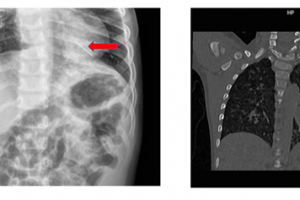

Cấp cứu một trẻ hóc dị vật đường thở là hạt hạnh nhân – Vừa qua, Bệnh viện Nhi Đồng Thành Phố tiếp nhận một trường hợp trẻ L. T. H. 15 tuổi, nam, ngụ ở...